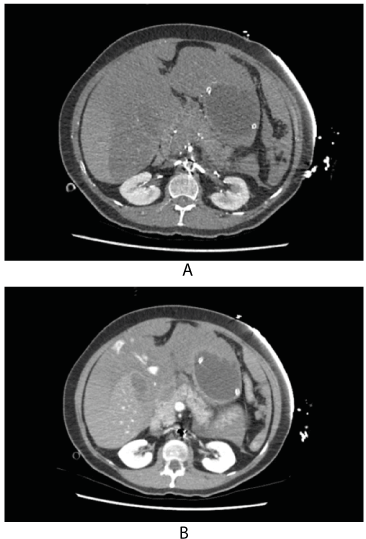

Following PCI, she remained hypotensive and tachycardic. Arterial blood gas revealed lactic acidosis: pH 7.09, pO2 42mmHg, pCO2 50mmHg, bicarbonate 15mmol/L, lactate 9.7mmol/L. Haemoglobin levels as measured on blood gases fell from 108g/L pre-PCI to 24g/L post-PCI. While cardiogenic shock was considered in the setting of myocardial infarction, the sudden significant fall in haemoglobin levels prompted suspicion of haemorrhage. The subcostal view of the echocardiogram performed in the cathlab revealed possible extra-cardiac collection of fluid and markedly reduced right ventricular volume; there was minimal pericardial effusion excluding pericardial tamponade as the cause of her hypotension (Figure 2). Meanwhile, it was noted that her abdomen began to swell up, suspicious of massive intraabdominal bleeding. The massive transfusion protocol was activated, and she was immediately transfused with multiple units of packed red cells. She was immediately transferred to the radiology department for an urgent CT scan of chest, abdomen, and pelvis. Her CT scanrevealed a large amount of hemoperitoneum and liver laceration involving segments 2, 3 and 4. There was active bleeding noted during the venous phase of the scan (Figure 3).

Figure 3. CT axial images showing haemoperitoneum and liver laceration: (A) arterial phase and (B) portal venous phase